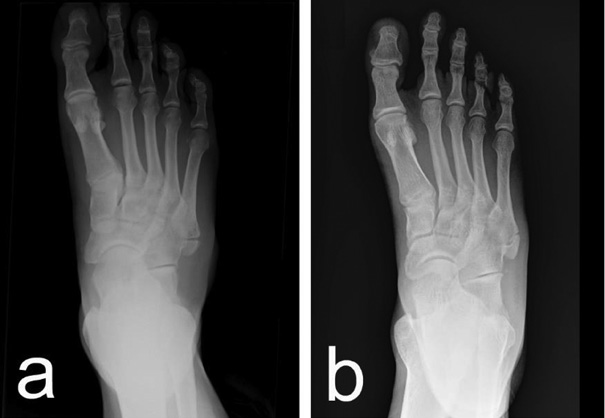

Initial plain radiographs revealed small bony fragments proximal to the base of the fifth metatarsal, which led to the preliminary diagnosis of an avulsion fracture. However, a detailed analysis by the specialist highlighted features inconsistent with acute trauma. The presence of a well-corticated, bean-shaped ossicle with smooth, rounded margins ultimately led to the correct diagnosis of OVP in both cases (Fig. 1).

OVP is a rare accessory ossicle that can be easily mistaken for an acute fracture, particularly in the context of lateral foot pain following trauma. Misdiagnosis may lead to unnecessary or inappropriate treatment. Our two cases highlight the importance of recognizing OVP based on its characteristic imaging features, well-corticated, smoothly contoured ossicles near the base of the fifth metatarsal. A thorough clinical examination combined with careful radiological assessment is essential for accurate diagnosis. Conservative treatment, including rest, ice, elevation, physiotherapy, and NSAIDs, proved effective, resulting in full functional recovery within three weeks. Increased awareness of OVP among clinicians is crucial for ensuring proper management and avoiding diagnostic errors.